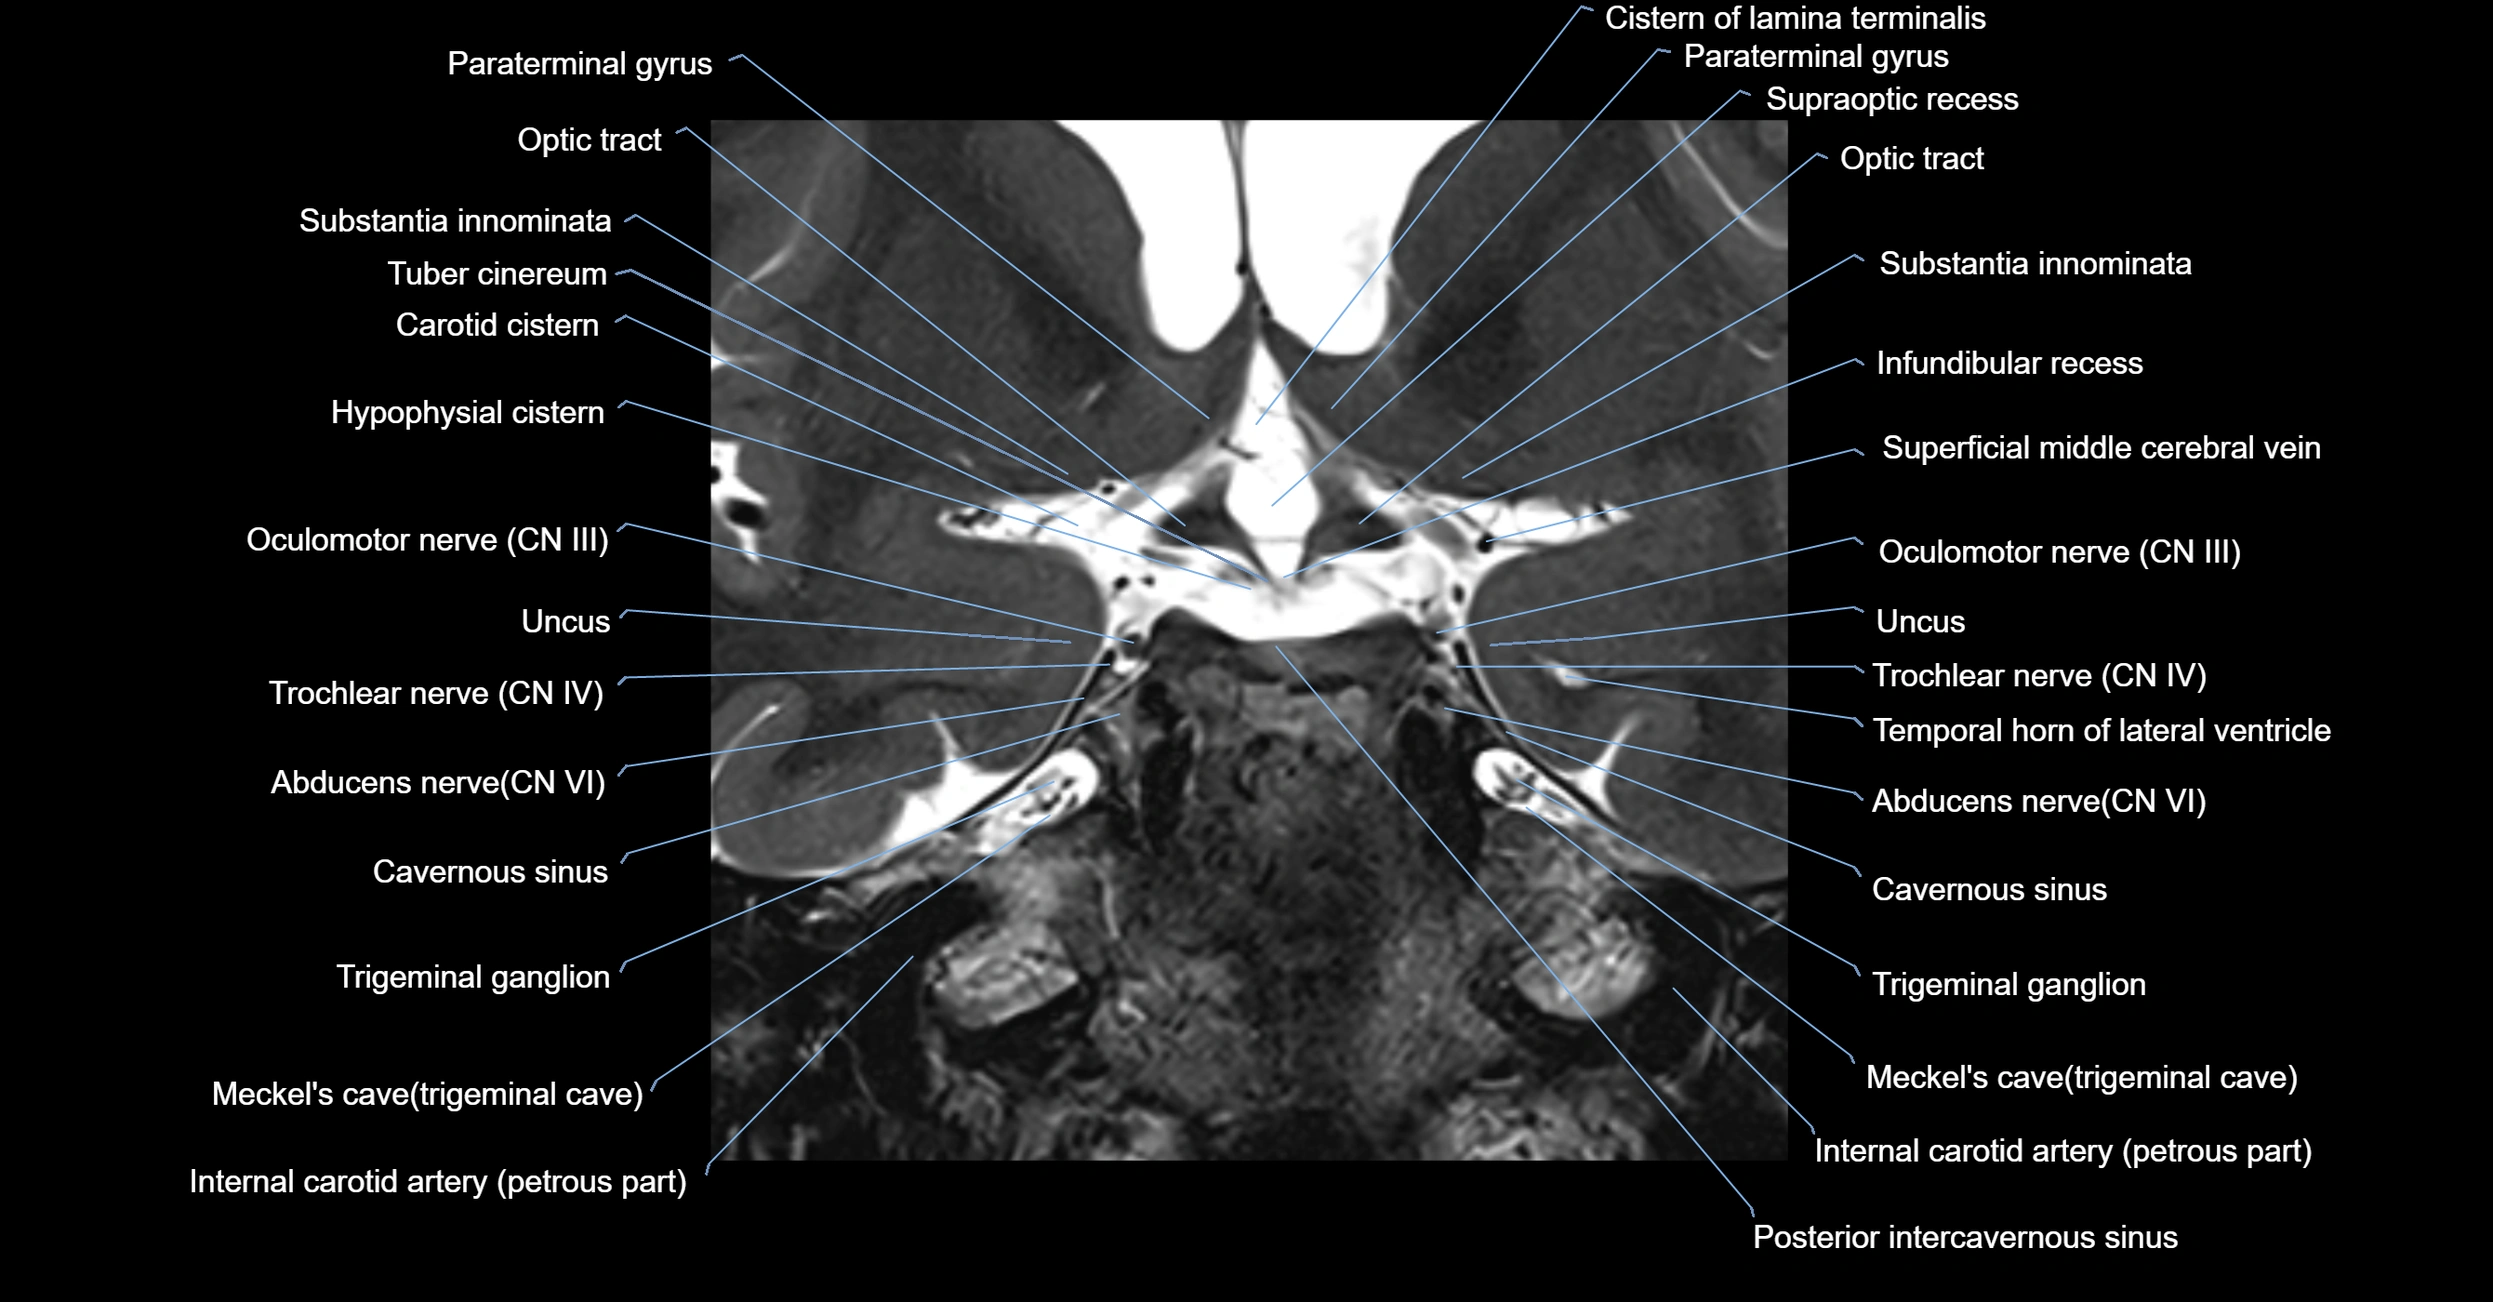

MRI Appearance

The abducens nerve is a small, thin, linear structure

Best visualized on high-resolution T2-weighted 3D MRI sequences (e.g., FIESTA or CISS)

Seen as a hypointense (dark) line running from the brainstem at the pontomedullary junction, traversing the prepontine cistern, and entering Dorello’s canal under the petrosphenoidal ligament, then into the cavernous sinus, and finally the orbit

May be challenging to visualize in standard MRI due to its small size

Pathology may be inferred by absence, displacement, or enhancement of the nerve

MRI images